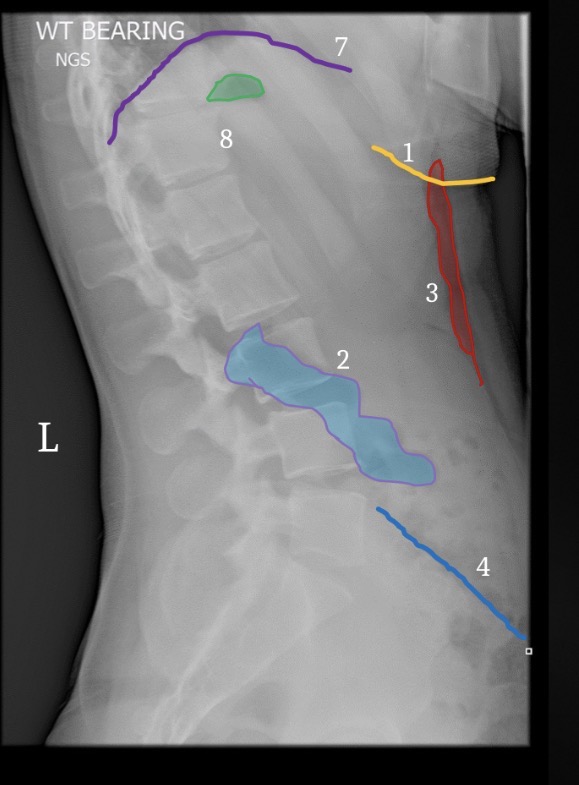

1

Right ilium

2

Left ilium

3

Right sacral ala

4

Left sacral ala